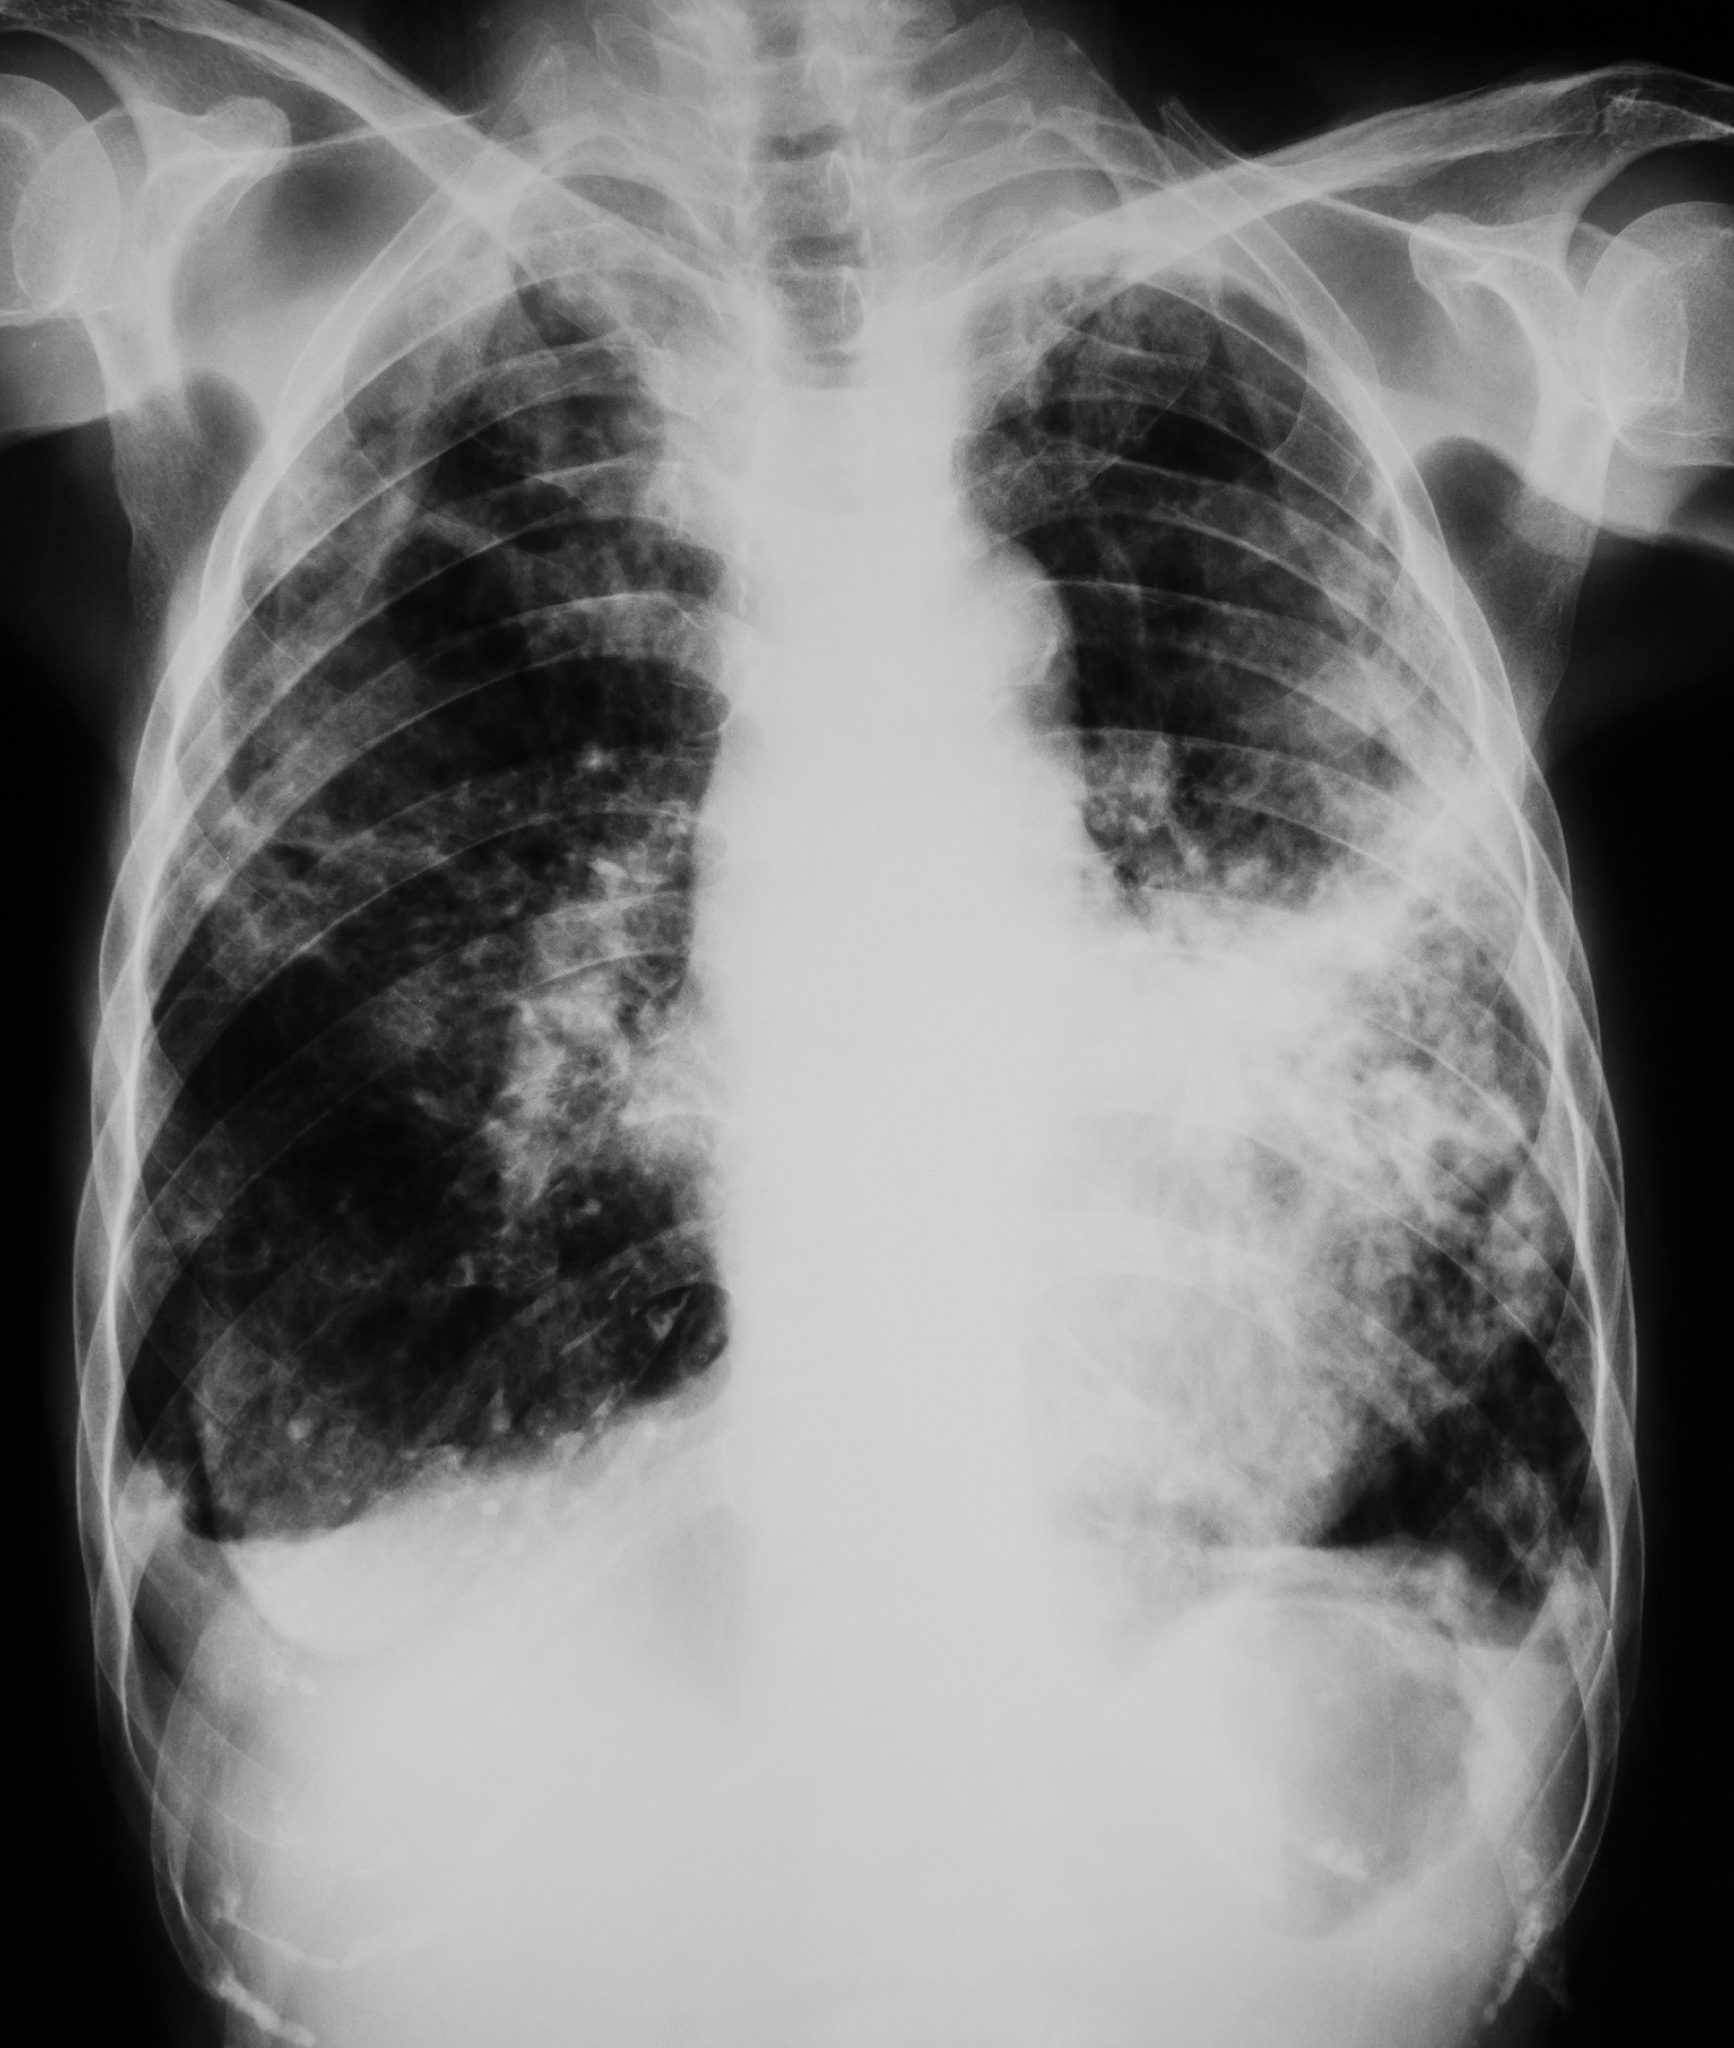

患者X线胸片示右肺上叶后段薄壁空洞直径4cm内有较小的液面空洞周围肺内有渗出病变右下叶及左肺中下野有多发斑片状渗出。最可能的诊断为

肺结核(空洞型)